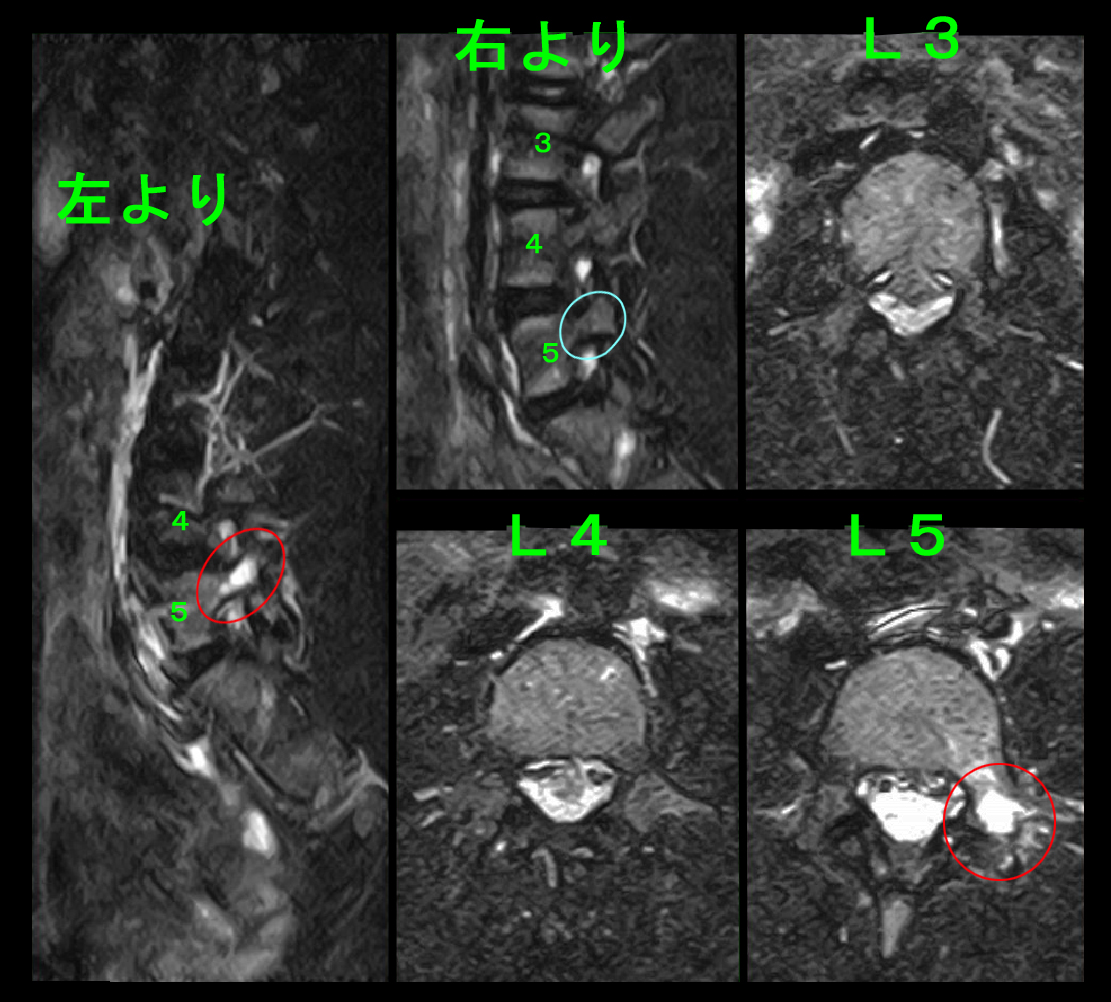

14才女 MR1.jpg

腰椎MRI検査の画像1ではL5-Sに軽微な椎間板ヘルニアが確認されます。

14才女 MR2.jpg

しかし、腰椎MRI検査2ではSTIRという骨が黒く描出される画像で、L5の腰骨の左寄りの赤丸部分で骨が白くなっており、これが腰椎分離症(腰椎の疲労骨折)の所見となります。腰椎分離症は体が硬い人に発症しやすい傾向があるため、分離症と診断した場合には椎間板ヘルニアより長い4週間の運動の休止と、体の柔軟性を高めるジャックナイフストレッチを指導しています。